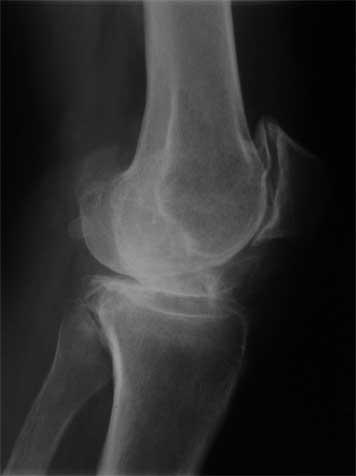

Alexander Rykov 16 Май 2009, 09:02

Похожее имело место в хирургии т.б сустава. Оказалось - эрозия небольшого

артериального сосуда (может пролежень). Ревизия и перевязка - и все завершилось благостно. Я бы выполнил ангиографию, все - таки артериальная

кровь. При повторном гемартрозе - ревизия: снять вкладыш - посмотреть сзади. Вариант диагностической

артроскопии не исключается. С ув. А Рыков Хабаровск.